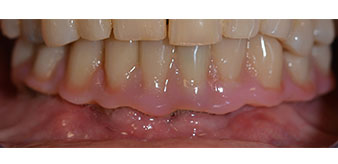

The impression and bite registration were then performed so that the dental technician could begin producing the provisional restoration immediately. This was then screwed in on the same day (Fig. 17 and 18).

Implants

Fig. 17

Fig. 18